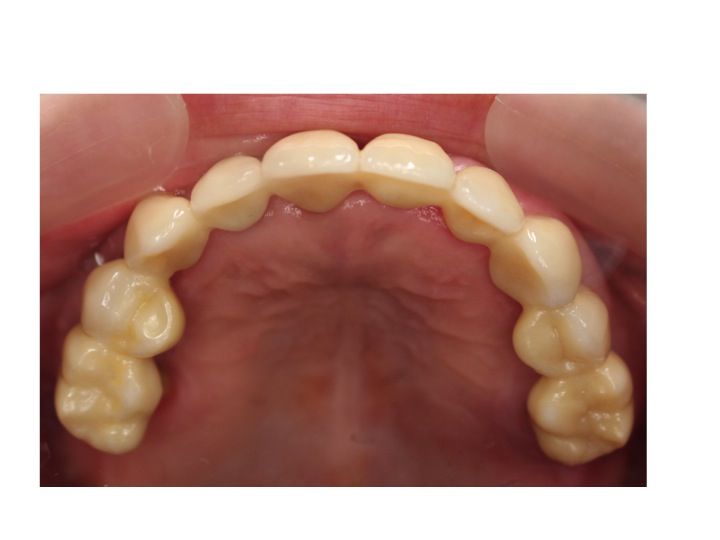

被せ物の材質がよくわかるように

噛む面(上顎を噛む面からみた状態です)からの写真です。

現在の場合には、以下のようにジルコニアを使用した被せ物を作製することが多くなりました。

審美性も良いです。